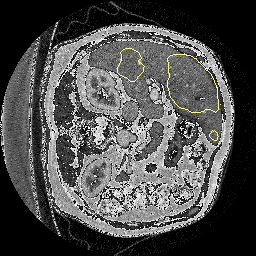

최종 결과는 훈련 데이터는 거의 100%, 시험 데이터는 약 80% 정도로 과적합이 일어난 것으로 보입니다. 만약 이를 발전시켜서 과적합을 방지하려면 몇 가지 규제 기법을 적용하거나 데이터를 추가하는 방법을 생각해볼 수 있습니다. 가장 좋은 방법은 data augmentation이겠네요!! 이 아티클에서는 시험 데이터를 예측한 결과의 경계선을 함께 보여줄 수도 있습니다.

저기 보이는 노란색 경계선이 예측한 결과입니다. 하지만, 실제 간과 많은 차이가 있음을 볼 수 있습니다. 따라서 아직은 성능이 좋지 않은 것을 볼 수 있습니다.